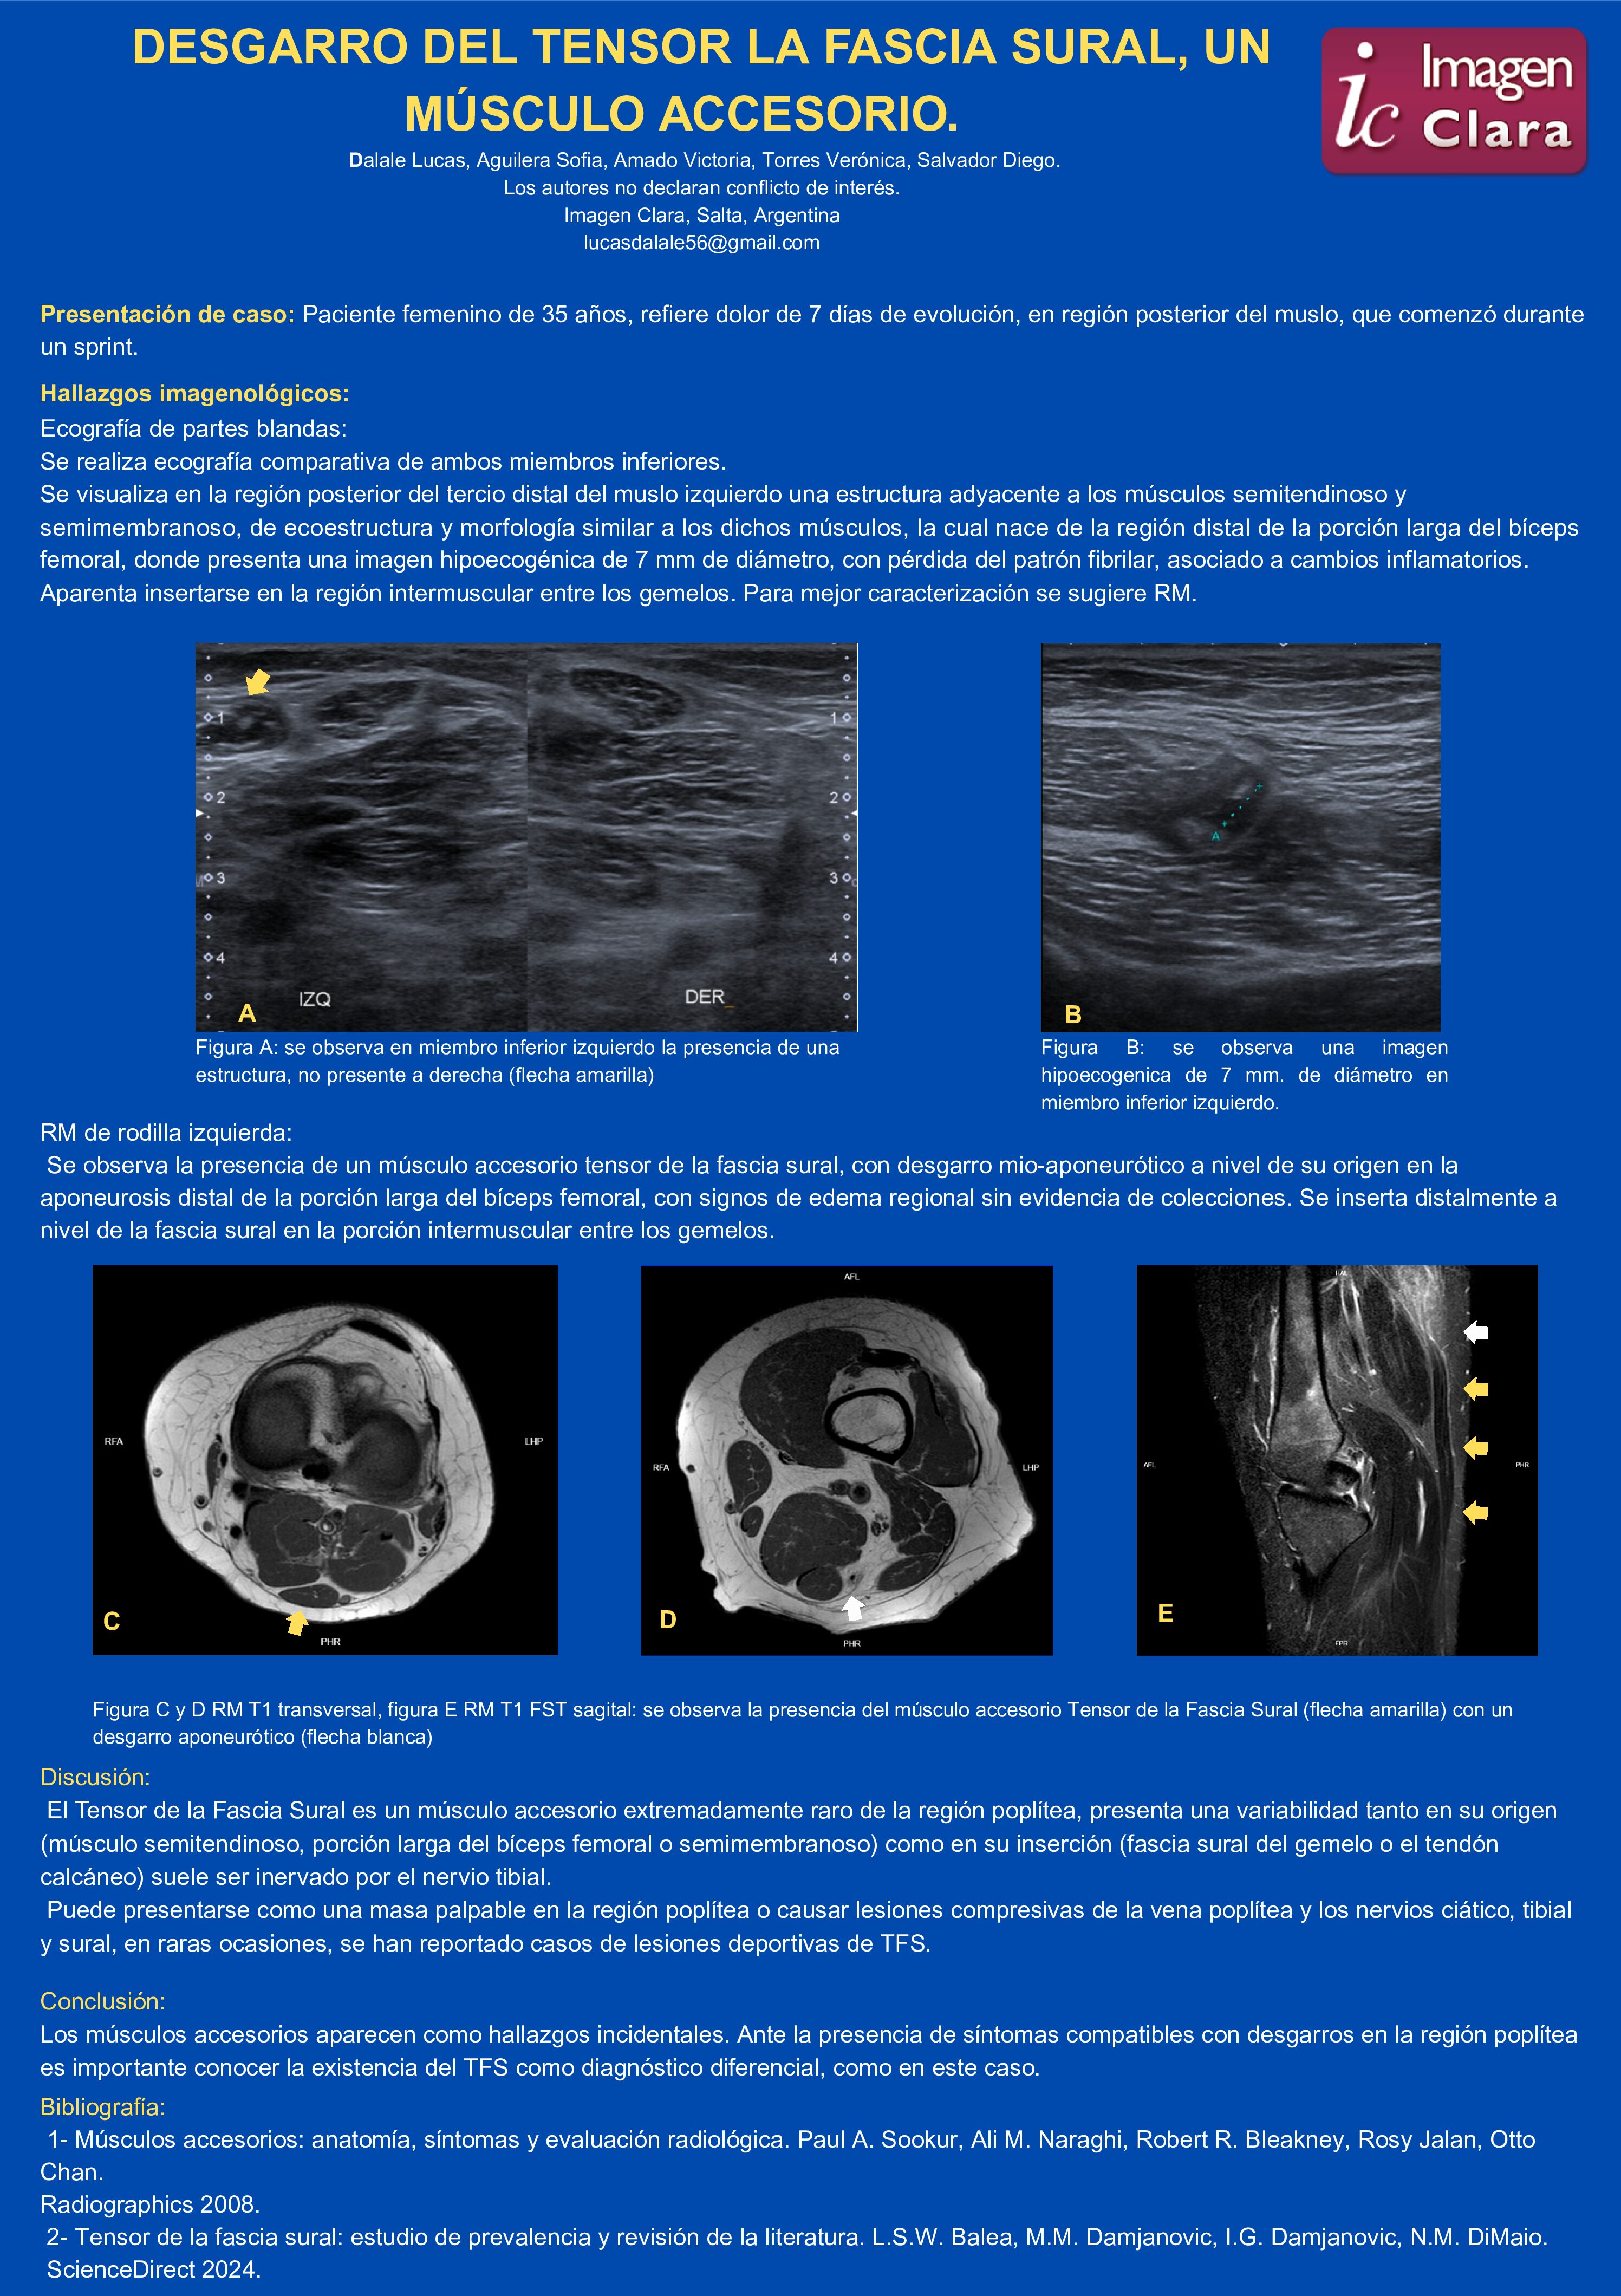

DESGARRO DEL TENSOR LA FASCIA SURAL, UN MÚSCULO ACCESORIO.